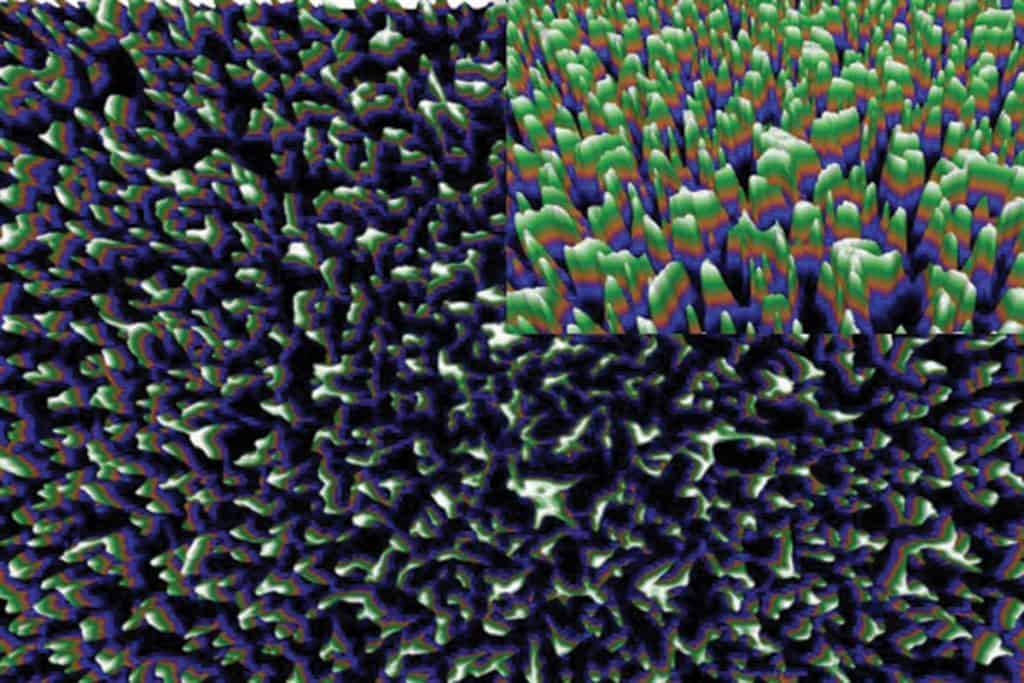

Les pics à la surface des ailes. Image: Ivanova et AL.

Pour concevoir des matériaux plus sécuritaires, une équipe montréalaise se tourne vers… les libellules et les cigales ! Et plus précisément vers leurs ailes, qui sont naturellement antibactériennes. « Elles sont couvertes de minuscules picots, sorte de nanoclous qui tuent les bactéries par contact physique », a expliqué Dao Nguyen, chercheuse à l’Institut de recherche du Centre universitaire de santé McGill, au cours d’un symposium de l’Initiative interdisciplinaire en infection et immunité de McGill en juin dernier. Plusieurs équipes s’intéressent à cette approche « mécanique », alors que les biofilms, enchâssés dans une gangue collante et protectrice, ont une capacité extrême à résister au système immunitaire. Ces communautés de microorganismes sont aussi de 500 à 5 000 fois plus résistantes aux traitements antibiotiques que les bactéries de même nature isolées.